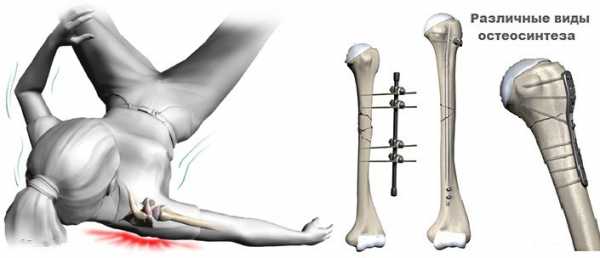

Оперативный остеосинтез проводят с применением фиксирующих конструкций разных форм и размеров, внутрикостных стержней. Сращивание кости в послеоперационный период длится до 3−5 месяцев в зависимости от тяжести смещенного перелома плеча. В сложных случаях необходимо повторное вмешательство, что повышает риск осложнений.

- Перелом плечевого сустава без смещения лечится при помощи шины, которая накладывается на травму сроком на два месяца. Если присутствует смещение, то прибегают к помощи скелетного вытяжения. В обездвиженном положении потерпевшему придется провести месяц. После этого на такой же срок будет наложен гипс. В последнее время лечебную методику скелетного вытяжения замещает остеосинтез, который не приковывает больного к постели на столь длительный срок.

- Перелом плеча со смещением — обломки закрепляют специальными стержнями, а через время, пока не срастется перелом, вынимают их из кости.

- Если имеется невправляемое обычным путем повреждение, то применяют пластиночную фиксацию без гипса с последующим снятием.

- Перелом тела со смещением – во время операции в кости вставляют внутрикостные стержни сроком на палтара месяца. При реабилитации лечение перелома плечевой кости продлевается на такой же срок.

- Травму чрезмыщелковых концов, сопровождающуюся смещением обломков вправляют под наркозом с наложением гипса на два месяца. Если смещение не удалось устранить, то проводят операцию, во время которой используют винты, пластины. Ставят их на несколько лет

- Перелом сложных, открытых травм тела лечат при помощи конструкции Илизарова, которая позволяет с самого начала терапии шевелить рукой. Данная конструкция держится на конечности около полугода.

Оскольчатые переломы плечевой кости могут возникать в любых отделах сегмента. Причиной обычно становится падение на руку, реже – удар или выворачивание руки. При повреждении верхней трети (переломы головки, переломы шейки плеча) наблюдается отек и деформация плечевого сустава. Движения в суставе резко ограничены, крепитация может не выявляться. Переломы проксимальных отделов, как правило, протекают относительно благоприятно. Обычно хорошего результата удается достичь с использованием консервативных методов – репозиции и последующей фиксации. При невозможности сопоставить отломки выполняется остеосинтез головки плеча винтами либо остеосинтез хирургической шейки плеча пластиной или спицами.

Тактика лечения выбирается с учетом осложнений и данных рентгенографии плечевой кости. При повреждении артерии показана неотложная операция. В остальных случаях обычно проводят репозицию либо накладывают скелетное вытяжение. Если отломки не удается сопоставить, осуществляют остеосинтез диафиза плечевой кости пластиной или спицами. Хирургическое вмешательство по восстановлению нерва обычно производят в отдаленном периоде. При отсутствии натяжения показан шов нерва, в остальных случаях – пластика поврежденного нервного ствола.